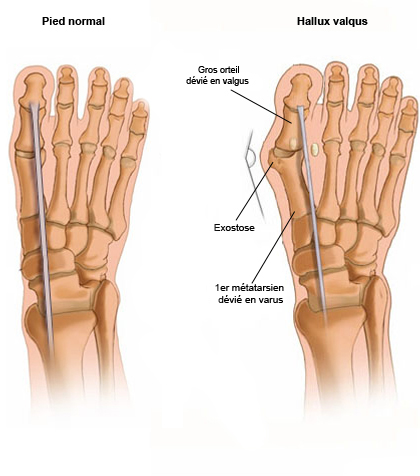

무지외반증이란 엄지발가락의 변형과 그로 인한 관절의 통증을 일컫는 질환이에요. 무지, 즉 엄지발가락이 새끼발가락 쪽으로 휘면 발 안쪽이 돌출되고 그 부위가 계속해서 신발과 닿게 되면 염증이 생기고 통증이 유발되어요.

무지외반증 증상은 첫째, 엄지발가락이 휘고 둘째, 발 내측 부위에 통증이 있으며 셋째, 통증 부위가 붉은색을 띄고 넷째, 엄지발가락을 제외한 나머지 발가락들이 저릴 수 있으며 다섯째, 제대로 걷기 힘들다 등으로 요약해볼 수 있는데요. 아래와 같이 무지외반증 증상을 네 단계로 나누어볼 수도 있어요.

무지외반증 수술은 엄지발가락이 돌출됨에 따라 타이트해진 엄지발가락 바깥쪽을 늘려주고 반대로 늘어난 엄지발가락 안쪽을 타이트하게 잡아주어 발가락의 본래 모양을 되찾아줘요. 또한 발등 뼈를 평행 이동시켜 발 폭을 줄여주고요.